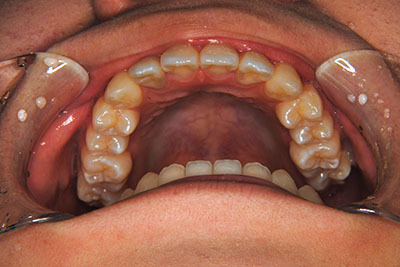

小学生高学年や中高生で矯正治療を考えている方へ

歯が乳歯から永久歯に生え変わった小学生高学年や、中高生でも矯正治療に手遅れということは全くありません。

成長中の顎の骨を矯正できたり、この時期の矯正はおとなになってから矯正治療を始めるよりも短期間で済むことがほとんどです。当院だとおおよそ1年で動的治療(マルチブラケット装置をつける期間)が終わることが多いです。